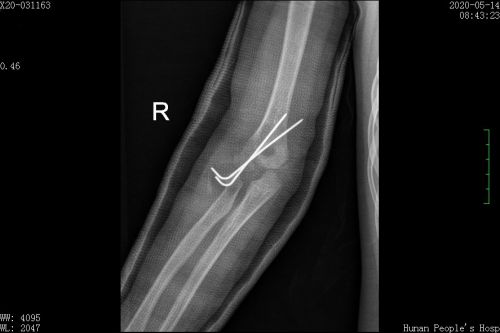

右侧肱骨外髁骨折闭合复位克氏针固定及石膏固定术后。